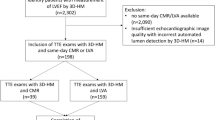

This prospective cross-sectional observational study was conducted from January 2021 till May 2022 at the Cardiology department of the Catharina hospital, Eindhoven, the Netherlands. Patients who needed standard of care transthoracic echocardiography were sent to the echo lab of the Catharina Hospital by their referring cardiologist. Exclusion criteria were age below 18 years, poor delineation of the endocardial border on SE images, (supra)ventricular arrhythmias, moderate to severe valvular disease, and moderate to severe pulmonary hypertension. Written informed consent was obtained from all patients. This study (W21.051) was approved by the institutional review board of the Medical Ethical Centre of Utrecht the Netherlands and carried out in accordance with the declaration of Helsinki.

Statistical analysis

A sample size calculation was performed to limit the width of the 95% confidence interval (CI) around the standard deviation (SD) of the bias to 10%. Based on a mean SV of 60 ml and a mean error of 30%, a sample size of 32 patients was calculated to be sufficient [10, 11]. We included 43 patients in order to account for a potential drop-out rate of approximately 25% due to insufficient image quality.

Fourty-three patients participated in this study, of whom 7 were excluded because of poor endocardial delineation of SE images, and 36 patients were included for analysis. The HAND, SE and 3DE measurements were performed in triplicate in thirty-six, twenty-two and thirty-two patients respectively. For the remaining patients, measurements were performed in duplicate. The mean value of the triple c.q. double measurements per patient are used in the analysis. The baseline characteristics of the patients are presented in Table 1. Endocardial borders were traced correctly in 100% (AS) and 96% (DHM) of the images. Image quality of SE and HAND was significantly different for A4CH images (10.49 ± 1.72 and 9,42 ± 1,96 respectively, p < 0.001) and for A2CH images (9.82 ± 1,99, and 8,49 ± 2,07 respectively, P < 0.001).